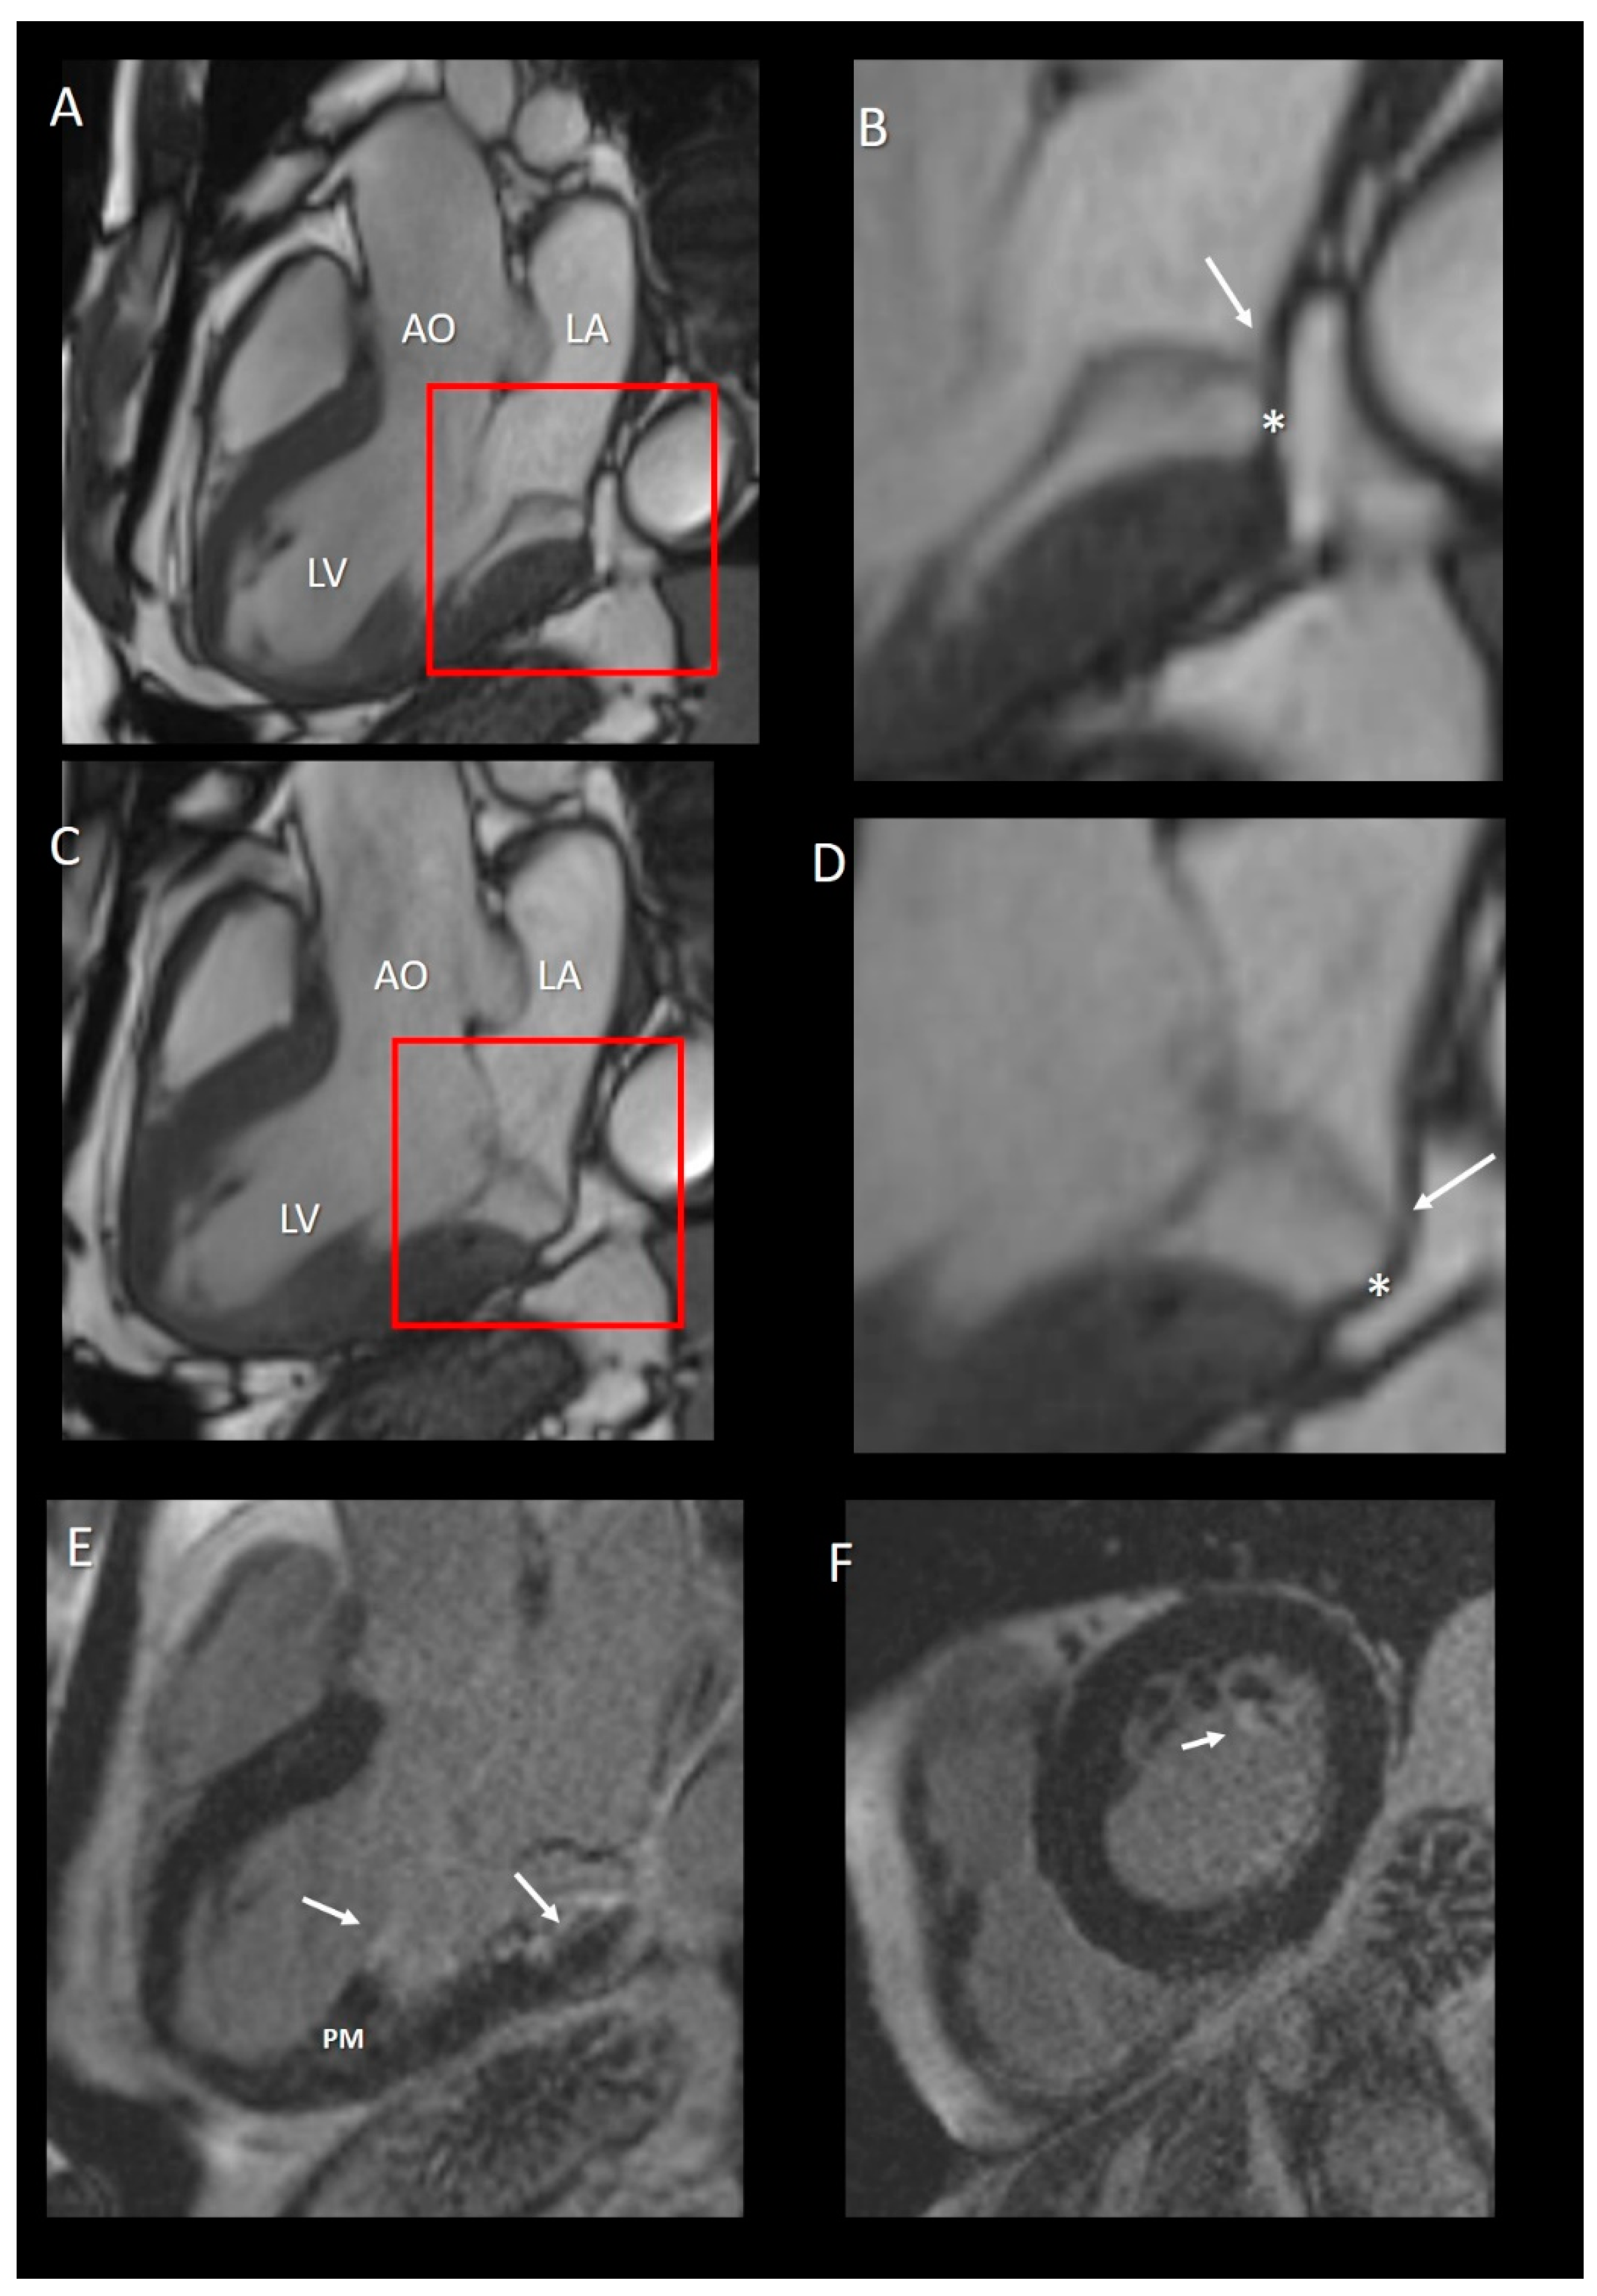

6.1.3. MA Disjunction

In an autoptic study based on 900 hearts, Hutchins et al. [30] found in 23 out of 25 hearts with bileaflet mitral valve prolapse (MVP), an anomalous arrangement of the hinge line of posterior leaflet: instead of being inserted on the junction of atrial and ventricular myocardium, the posterior leaflet was attached only on atrial myocardium creating an unusual “valvular-atrial junction” (Figure 10A–C). They called this arrangement mitral annulus disjunction (MAD). Interestingly, the space between the leaflet insertion and the crest of ventricular myocardium is replaced by a curtain-like fibrous tissue. Angelini et al. [12] found this atypical anatomy not only in hearts with prolapse and redundant leaflets, but also in hearts with morphological normal leaflets. MAD went unnoticed for several decades until Perazzolo Marra et al. [31] and Basso et al. [32] provided evidence that it was almost constantly present in those patients in whom MVP was associated with complex ventricular arrhythmias. This study added a new piece in the long-standing debate on arrhythmogenic MVP. Authors hypothesized that this particular arrangement would determine a myocardial stretch on those regions anatomically and functionally connected with the valve, specifically on papillary muscle (PM) tips and on basal ventricular myocardium, enhancing the propensity of MVP to cause arrhythmias. This hypothesis was confirmed by CMR and autoptic studies that demonstrated the presence of fibrous tissue either on the tip of papillary muscles or on basal ventricular myocardium. More recently, Dejgaard et al. [33] found that severe arrhythmic events, such as aborted cardiac arrest or sustained ventricular tachycardias, were related to MAD either in the presence or in the absence of MVP. Interestingly, MAD patients without MVP were more likely to have experienced severe arrhythmic events than patients with MVP. In other words, the MAD and MVP may be considered separate diseases. Further studies in larger and unselected populations are required to confirm if MAD itself is an arrhythmogenic entity.

Figure 10.

(A,C) CMR images in long-axis view in diastole (A) and in systole (C). (B,D) Magnified images of the structures in the red squares in panel A and C, respectively. The insertion of posterior leaflets on the atrial myocardium (arrow) is well visible either in diastole (panel B) or in systole (panel C). The asterisks in both B and D panel mark the curtain-like fibrous tissue. (E) Long-axis view late gadolinium enhancement (LGE) showing the fibrosis on the tip of papillary muscle (PM) and at the base of LV (arrows). (F) Short-axis view LGE showing the fibrosis on the tip of PM.